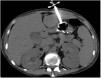

Ocho horas tras el procedimiento se inició nutrición sin resistencia a través de la sonda; la paciente presentó dolor abdominal intenso a la exploración, sin respuesta inflamatoria sistémica ni signos de irritación peritoneal. Los laboratorios no mostraron descenso de hemoglobina ni leucocitosis, únicamente trombocitopenia ya conocida (88,000 plaquetas). Al persistir con síntomas se solicitó TAC de abdomen, identificando el trayecto de la sonda a través del segmento III hepático y con el botón interno intragástrico, no se observaron datos de sangrado ni perforación (figs. 1 y 2).

Por el riesgo de sangrado y el pronóstico de la enfermedad de base, se decidió no retirar la sonda. La paciente permaneció estable y sin dolor, por lo que una semana después se realizó una TAC abdominal con contraste a través de la sonda, sin evidencia de fugas y con adecuado paso del mismo hacia la cámara gástrica (fig. 3).